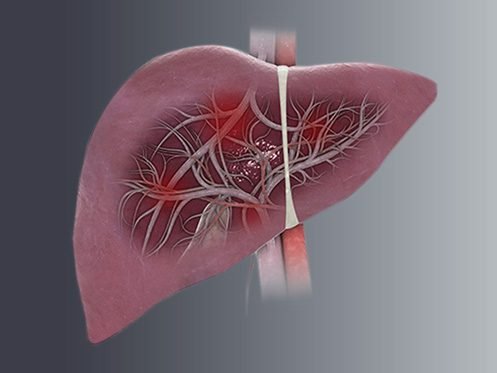

Saiba o que é colangite esclerosante primária

A colangite esclerosante primária (CEP) é uma doença inflamatória crônica…

Entenda o que é colangite biliar primária e conheça o tratamento

A CBP é uma doença hepática crônica que acomete os…